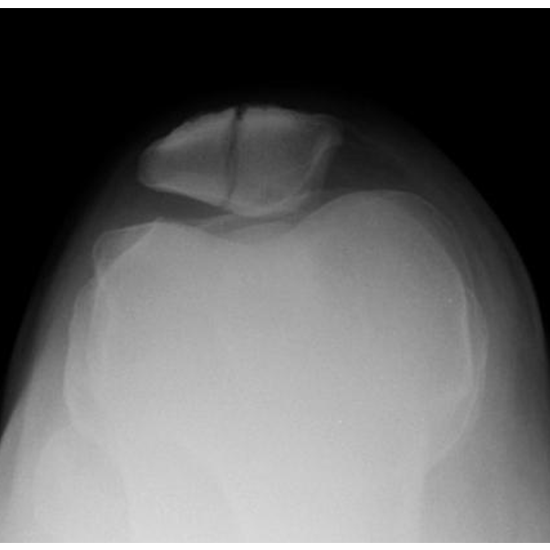

What is an X-ray Both Patella Skyline Axial Views Test?

X-Ray Both the Patella Skyline Axial Views assess the ability to visualize the knee cap. There is a triangular bone that covers the knee joint called the patella. The patella is connected to the lower end of the femur (thigh bone).